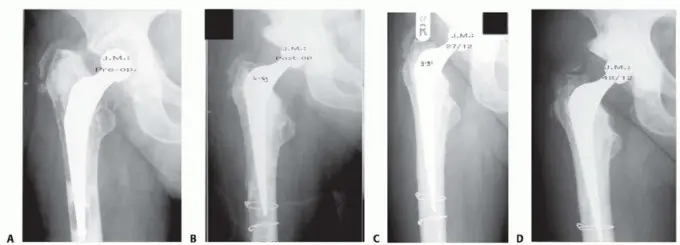

الصورة أعلاه (FIG 1) توضح جذعًا رخوًا مع تخلخل داخلي للعظم في (A)، ثم الحالة بعد الجراحة مباشرة (B)، وبعد 27 شهرًا (C) مع ملاحظة شفاء القشرة العظمية، وبعد 48 شهرًا (D) مع الحفاظ على جودة العظم الجيدة. هذه الصور توضح كيف يمكن لتقنية تطعيم العظام بالضغط أن تعيد ترميم العظم بفعالية.